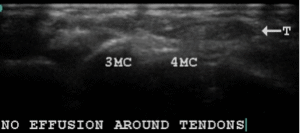

Figure 16 USG showing muscle regeneration at 12 days

The USG images on 6th December show that there are no clear outlines for muscles which are hyper echoic. The same hand on December 18th after 6 sessions of USGDN shows return of clear muscle outlines, with islands of hypoechoic muscle tissue in the hyperechoic fibrotic mass.